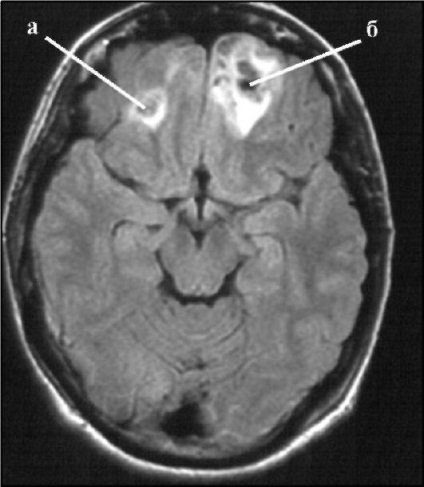

diagnosticare

În plus față de inspecție și a clarifica circumstanțele prejudiciului, este important de a face un diagnostic pe tomografie computerizata (CT). Un studiu efectuat pe echipamente destinate diagnosticului de leziuni cerebrale traumatice. Notă Tomograph mici abateri în materia creierului, permite să recunoască în mod corect tipul de leziuni, semne de hemoragie cerebrală, dimensiunea, de a identifica deteriorarea osului craniului. Uneori, o puncție lombară, EEG și altele.